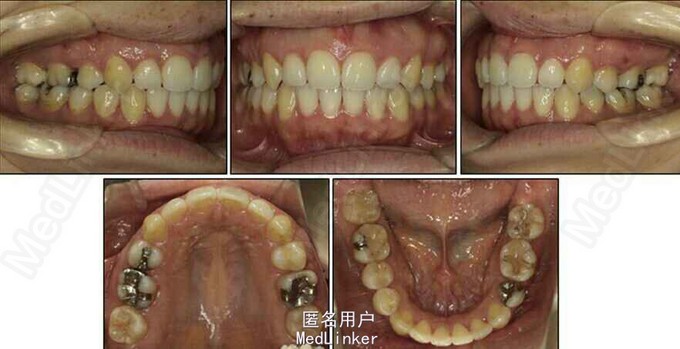

面部:凸面型,上下唇前突,上唇E线前3.5mm,下唇E线前9.5mm,闭唇时口周肌肉紧张。口内检查:双侧尖牙磨牙I类关系,左侧7锁合,覆盖4.5mm,覆合1mm,中线正,上颌拥挤度12.5mm,下颌拥挤度8.2mm。全景片示4个第三磨牙均阻生,怀疑上颌第二磨牙远中面因8阻生有牙根吸收,下颌8近中倾斜阻生更严重,右下6、左下4和5都行了RCT并大面积充填。头影测量示骨性I类,高角,下切牙唇倾。无TMJ症状,只是咀嚼测试时,右侧(非锁合侧)较左侧速度更快且更稳定。

诊断:安氏II类1分类,双颌前突,牙列严重拥挤,左下7锁合,双侧上7牙根吸收,四颗第三磨牙阻生 治疗目标:减少唇的突度及前牙拥挤,扶正4颗阻生的第三磨牙,达到良好的面部美观和功能咬合。 治疗:上颌拔除2颗5和2颗7(不拔4的原因为左上4为正常牙,左上5大面积充填;右上4形态较右上5好。因拔除了坏牙保留了健康牙齿,但是拔5不利于前牙的内收,所以于上后牙56之间植入了支抗钉加强支抗,辅助内收前牙。拔7原因为两颗7远中面均有牙根吸收且有大面积充填),下颌左侧拔除5和7(左下5根管治疗且根尖阴影,拔除左下7原因为严重锁合,改正困难且容易导致上下磨牙的伸长加重II类高角面型),右侧拔除根管治疗且大面积充填后的6;分别竖直4颗近中倾斜阻生的8,整个疗程39个月,四颗8成功的代替6或7。双侧I类尖牙关系,左侧磨牙I类关系,右侧磨牙完全远中关系。唇突度改善,全景片可见达到可接受的牙根平行度,4个8完全萌出直立。以前因为锁合导致的两侧咬合不对称没有了。